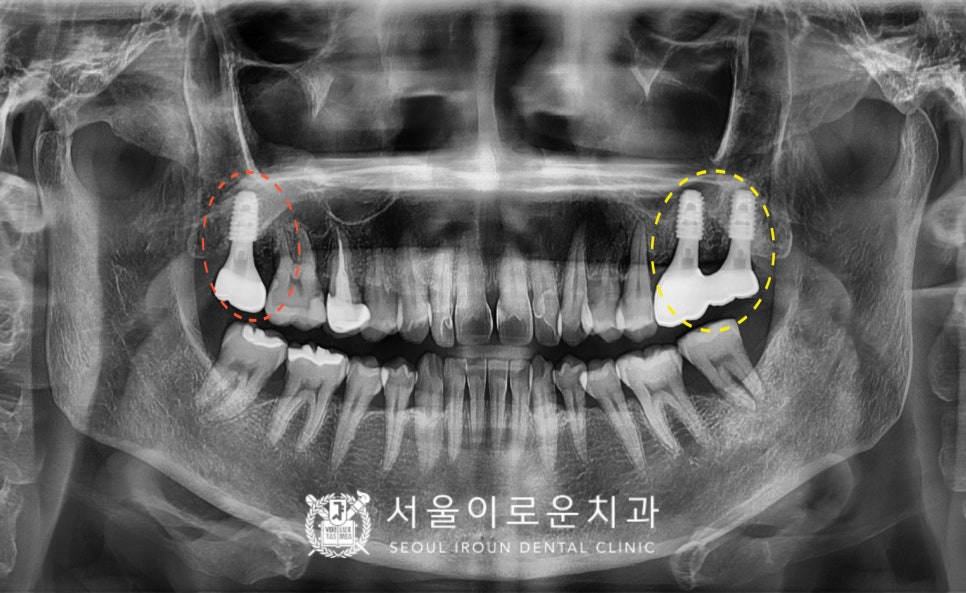

정밀한 검사를 위해

파노라마 사진을 촬영해 보았더니,

✅ 노란색 동그라미 표시의

위턱 왼쪽 큰 어금니 두 개(#26,27)는

심한 치주염으로 인해

2도 동요도를 보이고 있었는데요.

치아 뿌리를 잡고 있는 잇몸뼈가

염증으로 인해 흡수가 많이 되어 있어

살려 쓰기 힘들 것이라 판단되어

안타깝게도 발치 후

임플란트를 계획했습니다.

✅ 빨간색 동그라미 표시의

위턱 오른쪽 두 번째 큰 어금니(#17)는

발치하신지 상당 기간 지났으며,

잇몸뼈에서 상악동까지의

수직적 거리가 충분하여

별도의 뼈이식 없이

임플란트 식립을 계획하였습니다.

✅ 주황색 화살표 표시의

위턱 오른쪽 첫 번째 큰 어금니(#16)는

치아 사이 부분에 충치가 보였는데요.

이 충치로 인해 환.자분께서 평소

저작 시 날카로운 통.증을 보이셨습니다.